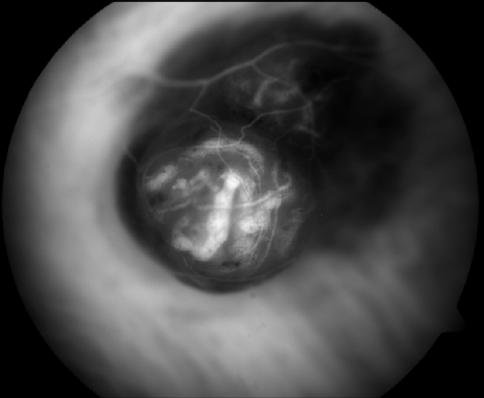

Gonio Photography

Iris Tumor

James Gilman, CRA, FOPS

Moran Eye Center

Salt Lake City, Utah

James Gilman, CRA, FOPS Moran Eye Center Salt Lake City, Utah